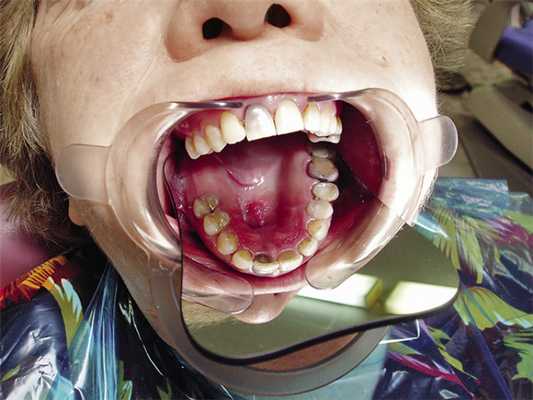

На кафедру ортопедической стоматологии из онкологического диспансера Екатеринбурга была направлена на консультацию пациентка Г., 64 лет, по поводу рецидива хондромы верхней челюсти (рис. 1).

Анамнез: 4 года назад была проведена первая операция по поводу хондромы верхней челюсти, месяц назад был поставлен диагноз: рецидив хондромы верхней челюсти. В полости рта в передней трети твердого неба отмечается безболезненный узел с неровной поверхностью размером 8х15 мм и сквозной дефект, сообщающийся с гайморовой пазухой размером 7х10 мм (рис. 2).

Рис. 2. Клиническая картина верхней челюсти (до операции).

Все это время пациентка пользуется частичным пластиночным протезом-обтуратором с проволочными гнутыми кламмерами (рис. 3).